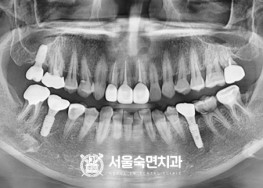

임플란트-치료-전후사진